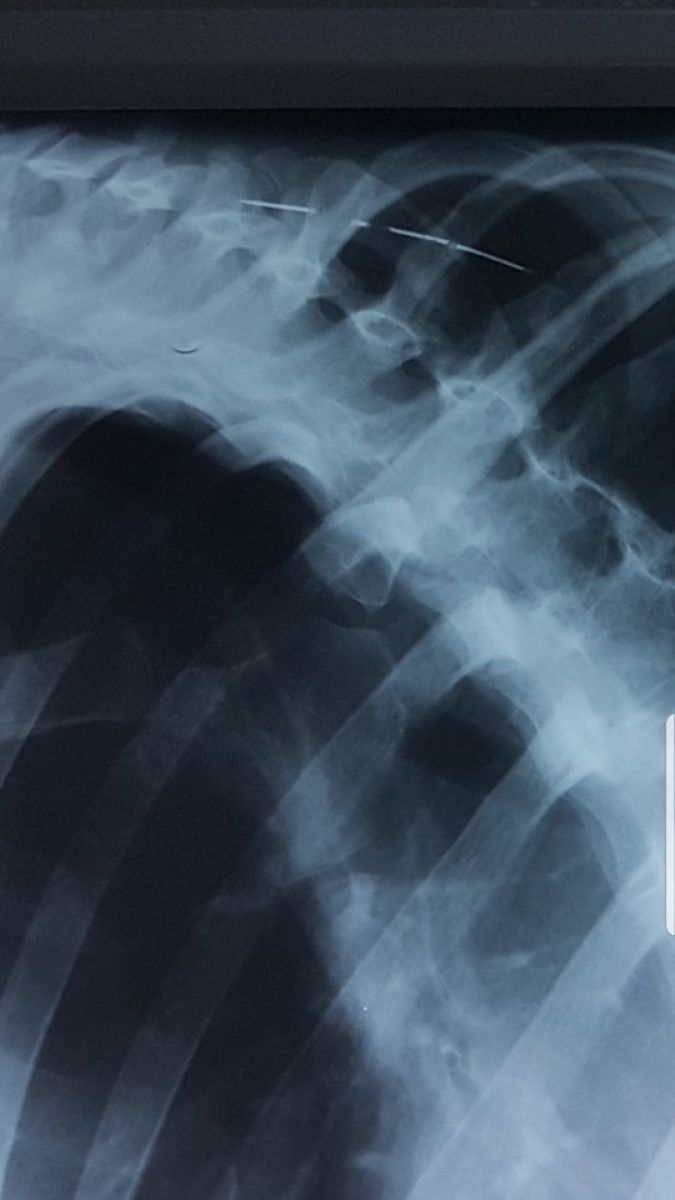

Ace, cuie și sârme au fost găsite în corpul unui pacient, imaginile fiind făcute publice de un medic din Botoșani. ”În 40 de ani de când mă învârt în ale medicinii nu am văzut așa ceva”, spune medicul Elena Cardaș, care a postat pe Facebook fotografiile, menționând că este vorba despre un pacient cu tulburări afective și psihice.

”Ce se mai poate găsi în corpul unui pacient. Ace, cuie, sârme. În 40 de ani de când mă învârt în ale medicinii nu am mai văzut așa ceva. Ca o precizare, este vorba de un pacient cu tulburări afective și psihice. Acele sunt de mult acolo, umăr, gât, axilă. Corpul le acceptă. Ce sa facă, săracul. Este o victimă”, a scris medicul Elena Cardaș.

Oamenii s-au arătat îngroziți de imaginile care însoțesc postarea. Fiind vorba despre persoane cu probleme psihice, manifestările de acest gen intră în sfera patologică. Potrivit celor precizate de medic, obiectele au fost introduse în corp de-a lungul vremii.

”Îi face plăcere când îl doare. Se automutilează ori de câte ori are ocazia”, a completat medicul Elena Cardaș.